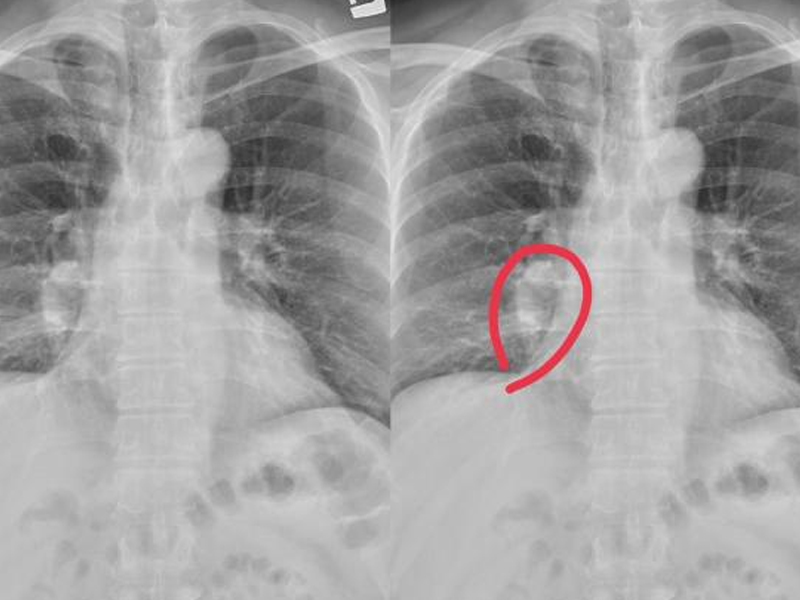

第四,杵狀指(趾)

表現為手指或足趾末端增生、肥厚、呈杵狀膨大。其特點為末端指(趾)節明顯增寬增厚,指(趾)甲從根部到末端呈拱形隆起,使指(趾)端背面的皮膚與指(趾)甲所構成的基底角等於或大於180°。

很多人把杵狀指與痛風或類風濕性關節炎混淆在一起,這是不正確的。

目前醫學界認為杵狀指的發病原因與缺氧和內分泌功能紊亂有關,先天性心臟病、胃腸疾病、肝硬化等都可能導致杵狀指。

還有,要警惕癌症所致,比如肺癌也是引起杵狀指的常見原因。